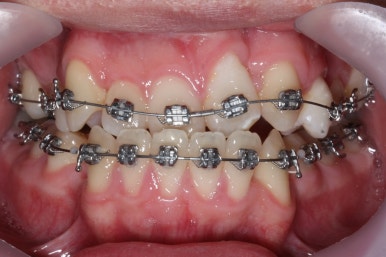

부산구순구개열 키다리아저씨치과에서 교정치료 하신지 1년여만에 드디어 앞니는 거꾸로 넘어왔고, 윗니들도 상당히 많이 가지런해졌습니다.

이 뽑은 자리도 상당히 많이 줄어든 것을 볼 수 있고, 이제는 정상적인 포개짐이 만들어졌습니다.

아래 치열은 거의 완료가 되었네요.

이 뽑은 자리도 다 없어졌고요. 대신 윗니는 어금니쪽에 약간의 틈과 기울어진 경사 등등 디테일한 조절을 계속해 나갑니다.

가장 최근의 사진입니다.

아직 치료 종료는 안되었으나 약간의 조절을 더하면 치료를 마무리할 수 있을 것 같습니다.

물론 윗니 한 쪽은 작은 앞니가 없고 한 쪽은 작은 어금니가 없기 때문에 중앙선이 100% 일치하지는 못하겠지만 기능적으로나 미적으로나 매우 개선되었음은 틀림없습니다.

치료 전과 가장 최근의 사진을 비교해 보겠습니다.

좌측이 부산구순구개열 전, 우측이 가장 최근의 사진들입니다.

거꾸로 물리던 앞니가 개선되었습니다.

좁아져 있고 찌그러진 위턱뼈의 형태가 개선되었습니다.

영구치 개수가 모자라는 선천결손이 있었지만 아랫니도 개수를 맞춰줌으로써 치아의 맞물림도 상당히 좋아졌습니다.